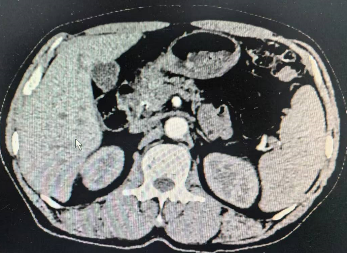

2024年7月CT结果 腹腔肿瘤消失

经过7个多月“漫长的等待”,患者于2024年7月再次入住老年普外科大明宫院区,术前再次行上腹部增强CT结果:胃窦壁稍厚,并浆膜外渗出性改变;横结肠局部壁厚,周围软组织增多,术前分期cTxNxM0,治疗后降期明显,已经符合手术根治性切除标准,如图二的CT所示。术前老年病MDT评估患者情况良好。做好术前准备后在大明宫手术室和麻醉科的配合下,2024年7月23日由科室主任王志东教授主刀,李运浩博士,金鑫住院医师协助进行完全腹腔镜下远端胃癌根治术,手术顺利,术后恢复顺利。术后病理显示胃癌病灶和淋巴结转移完全消失(图四所示),达到了医学上称之为的病理完全缓解(pCR)。知道这个结果后病人和家属都皆大欢喜,悬着的心终于放下了。术后1月来院系统复查仍然未见肿瘤复发和转移迹象,并再次进行了辅助治疗后顺利出院。